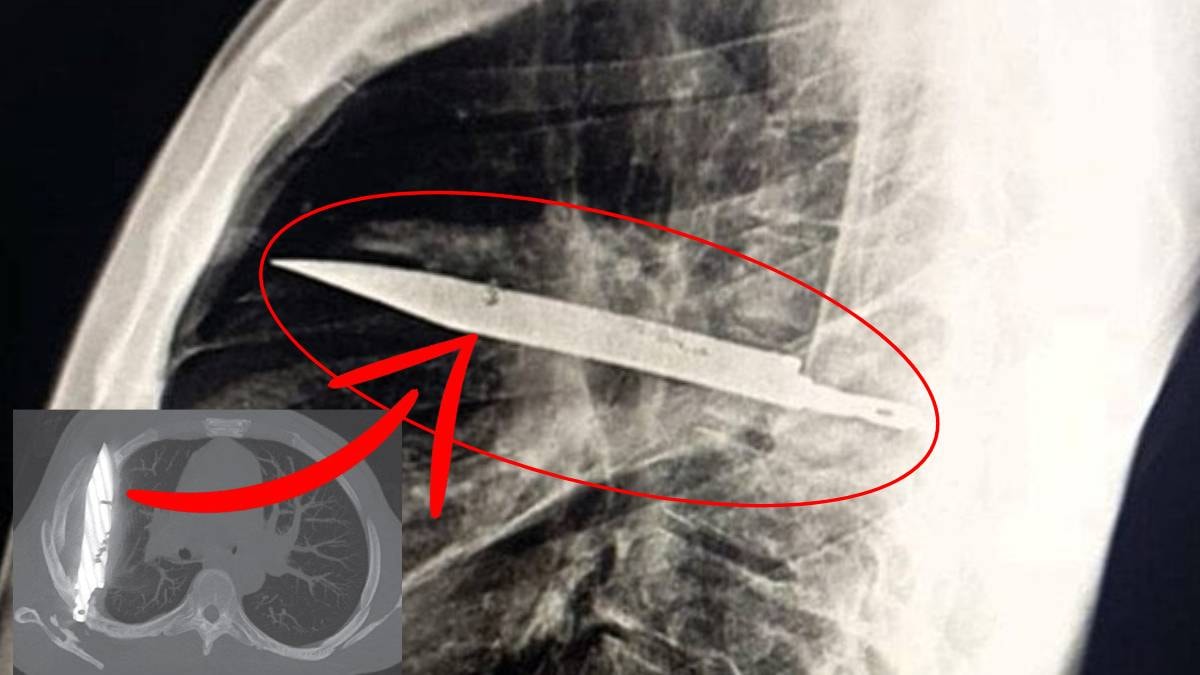

Çekilen röntgen, tüm semptomların nedenini ortaya koydu. Göğüs kafesinin içinde büyük bir bıçak bulunduğu anlaşıldı. Bıçak sağ kürek kemiğini delmiş, ancak hayati organlara zarar vermemişti. Doktorlar, gördükleri manzara karşısında büyük şaşkınlık yaşadı.